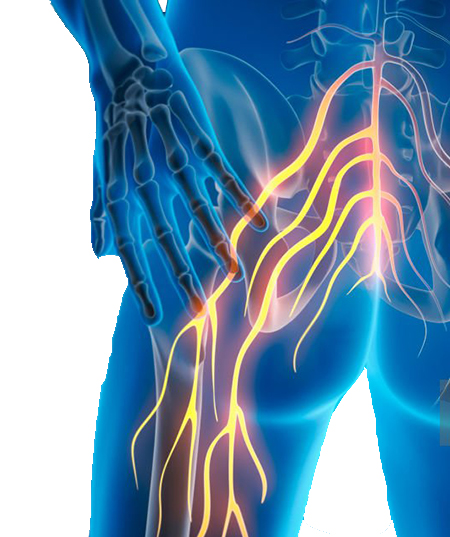

Sciatique

Lire